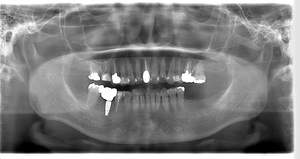

レントゲン写真

- Befor

- After

| 年齢 | 50代・男性 |

|---|---|

| 主訴 | 左上7番 左下5番7番 |

| 治療内容 | ・インプラント埋入 ※1:GBR(骨造成)・・・骨再生誘導法。骨の高さや厚みを人工骨や人工膜などを使用し再生する方法 |

| 治療費 | 合計:1,809,500円(税込) ■内訳 ・左上7番 ・左下5番7番 |

| 治療期間 | 左上7番約1年 左下5番7番約10ヵ月 |

| 治療方針 | 左上7番は昔他院で被せものをしており、被せものの中が歯ぐきの中まで虫歯になっていたため抜歯せざるを得ない状態だった。抜歯と同時に骨造成を行い、骨が出来るまで4ヵ月待ってからインプラントを埋入した。 ※2ポンティック・・・歯のない部分を補うダミーの歯。 |

| 担当者所見 | 元々金属の被せものが多く入っていたため、2次カリエス※3が多かった。今回は金属ではなく、ジルコニアを使用し、2次カリエスにならないよう、患者様にはブラッシング指導とメンテナンスの重要性をお伝えした。 ※3二次カリエス・・・詰め物や被せものを入れた歯が虫歯になること。 |